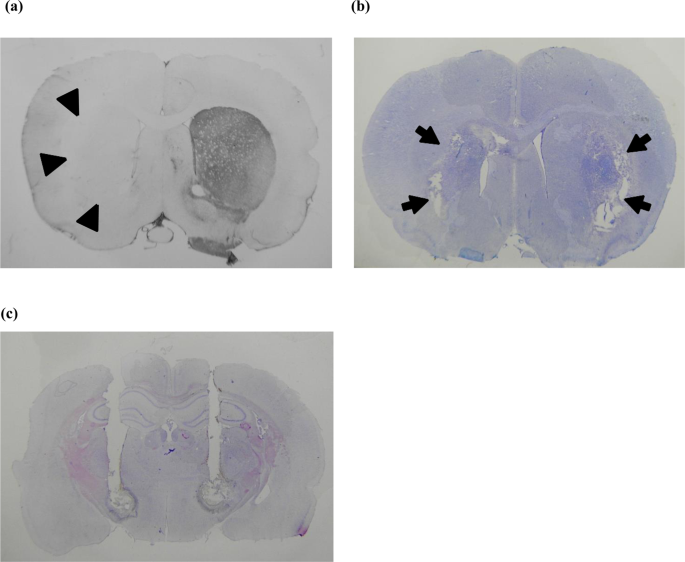

All of the rats were verified for the extent of loss of dopaminergic neurons in the SNc by tyrosine hydroxylase immunohistochemistry (IHC) after completion of the experiments (Fig. 1(a)). Tissue collection for IHC was typically performed 4–6 weeks after successful 6-OHDA injection. Two weeks after the successful creation of 6-OHDA lesions, a mixture of 20 mg levodopa/kg (Sigma, USA) and 5 mg benserazide/kg (Sigma, USA), both dissolved in saline, was injected into the parkinsonian animals via subcutaneous route every 2–3 days to induce dyskinesia (i.e., 3 injections a week, for a total of 4–6 induction injections). After the third or fourth administration of the levodopa/benserazide mixture, the parkinsonian animals usually showed levodopa-induced dyskinesia, which was assessed by the abnormal involuntary movements(AIMs) score. Basically, the AIMs score comprises a rating scale for 4 subtypes of abnormal movement, namely, limb, axial, orolingual and locomotive. However, we took only the first 3 measures for a more specific evaluation of dyskinesia19. The behavioral and electrophysiological data in the qualified rats (those with a total AIMs score 20, 40, 60,80,100 and 120 minutes after injection of levodopa ≥ 35) were then documented with a series of challenge injections (once every 2 or 3 days for a maximum of 8–10 challenge injections)19,20.

Histological verification of animal models of hyperkinetic movement. (a) Tyrosine hydroxylase immunohistochemistry showing unilateral deprivation of dopaminergic innervation of the striatum (arrowheads) in a parkinsonian rat with levodopa-induced dyskinesia. (b) Bilateral striatal lesions (arrows) in a rat with hyperkinesia after direct intrastriatal 3-NP injection shown by cresyl violet staining. (c) Cresyl violet staining showing trajectories of the combined microinjection cannula/stimulation electrode in the bilateral subthalamic region in a levodopa-induced dyskinesia parkinsonian rat.

Under Zoletil/Xylazine anesthesia, 2 µl of 1 µM 3-nitropropionic acid (3-NP, 99% pure; Sigma, USA) dissolved in saline was directly injected into the bilateral striatum (AP + 0.7 mm, ±ML 2.6 mm, DV −4.5 mm from bregma) of 9–10-week-old rats at a rate of 0.5 µl/min for 4 minutes to produce excitotoxic-like lesions in the bilateral striatum. Implantation of bilateral STN chronic stimulation electrodes was performed at the same time as the surgery for creating excitotoxic lesions. The stimulation electrodes (Plastics One, Roanoke, VA) were made of polyimide-insulated stainless steel (length 10 mm; diameter 0.250 mm) and were affixed to a threaded plastic pedestal with a stainless steel ground wire (diameter 0.125 mm). The ground wire was attached to a skull screw. The electrode pedestal was then fixed onto the rat head by bone cement, which was attached to 2–3 skull screws for fixation and chronic use. One week after the formation of bilateral 3-NP lesions, the rats were tested for locomotor behavior in an open field arena. The locomotor behavior tests were performed at a fixed time (i.e., 14:00~16:00) each day for a period of 1~2 weeks. After connection of the implanted stimulation electrode to a cable, each rat was habituated for 15 minutes in a quiet plastic chamber, and then the rats were individually placed in the open field arena (45 cm (w) × 45 cm (l) × 40 cm (h)) for the locomotor behavior test. For the intrastriatal 3-NP lesion-induced hyperkinesia model, we monitored 3 parameters of locomotor activity, including total movement distance, total movement duration and rearing score during the 5-minute test period. Specifically, the rats had two sessions of locomotor behavior tests on an experimental day, the first session with sham stimulation and the second with electrical stimulation, each lasting for 8 minutes. In each session, the experimental animal was first given a 3-minute stimulation (sham or constant positive current) in an incubation chamber, followed by another 5-minute test period, when the animal was placed in the center of arena and recorded to monitor locomotor activity under the two stimulation conditions. The amplitude of the constant positive current was set at 0 (sham stimulation), 75, 150, 300 or 450 µA. The locomotor activities of the rats were recorded by a digital video recorder (JVC, Japan) and analyzed using an Ethovision system (Noldus, Netherland). All of the rats were verified for the extent of neuronal loss in the striatum after completion of the experiment (Fig. 1(b)).

Implantation of the electrodes and electrophysiological recordings of the STN